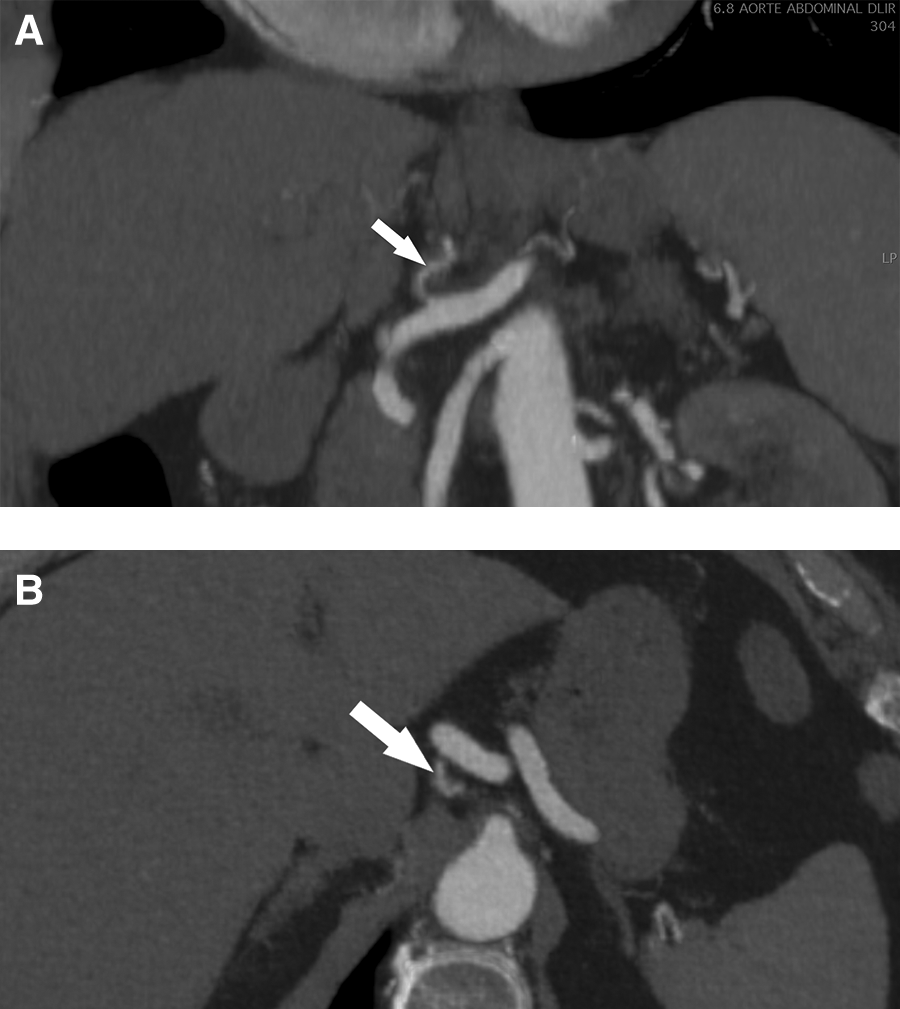

Based on these findings, conservative management was proposed, consisting of blood pressure control and close monitoring. The patient had no postprandial pain and was advised to eat normally as tolerated. Single antiplatelet therapy with aspirin at a dosage of 100 mg daily was initiated, and the patient was followed in an outpatient setting. Symptoms gradually improved, and the patient became asymptomatic after 7 days. A follow-up CTA at 6 months showed expansion of the true lumen of the LGA, and no secondary aneurysm formation or imaging signs in favor of fibromuscular dysplasia in other vascular beds were observed (Figures 2A,B). Based on these imaging findings and the absence of recurrent symptoms, antiplatelet therapy was discontinued following a multidisciplinary panel discussion.

Figure 2

Helicoidal 512 slice computed tomography angiography at 6 months in arterial phase with 1.3 mm slices. (A) Sagittal view of a less-thickened LGA (arrow) with near complete resolution of dissection. (B) Coronal view with a recanalization of the lumen of the LGA (arrow). LGA, left gastric artery.